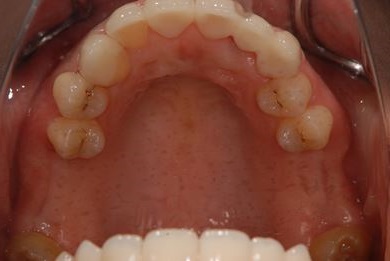

セラミック治療+骨造成(欠損部)

| 性別/年齢 | 女性 / 34歳 | ||||||||||||||||||||||||||||||||

| 治療方針 | 上顎前歯1歯抜歯し、オールセラミックブリッジ、クラウン、ラミネートベニアにて審美的回復を行う。 | ||||||||||||||||||||||||||||||||

| 治療内容 | オールセラミッククラウン2本、ジルコニアフレームオールセラミックブリッジ3本、オールセラミックラミネートベニア2本、骨造成(欠損部) | ||||||||||||||||||||||||||||||||